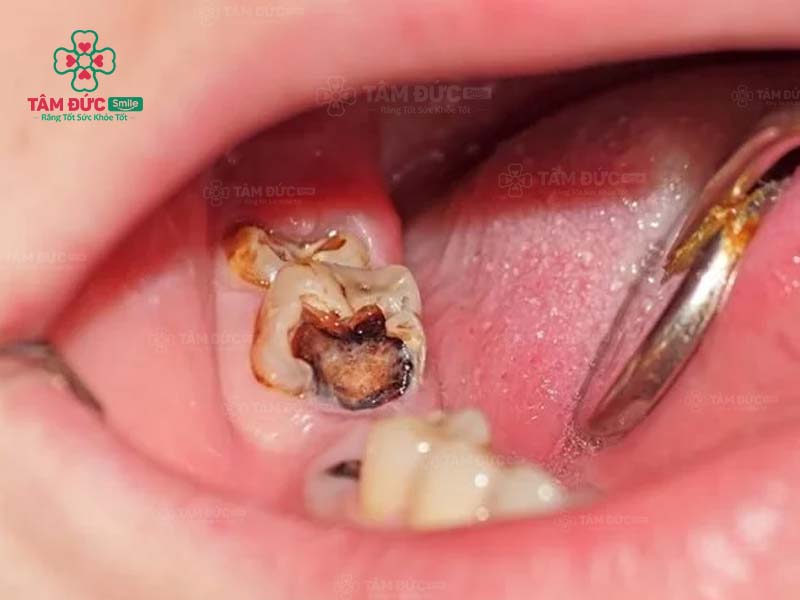

1.1. Răng bị sâu

Khi răng bị sâu, trên thân răng xuất hiện các lỗ nhỏ li ti. Đây chính là vị trí trú ngụ của hàng nghìn loại vi khuẩn. Cùng với thói quen chăm sóc răng miệng không tốt, ăn thực phẩm chứa nhiều đường, lỗ sâu răng sẽ lớn dần và gây đau nghiêm trọng. Nguy hiểm nhất chính là nhiễm trùng và mất răng vĩnh viễn.

Trám răng giúp lấp đầy các lỗ hổng trên thân răng. Nhờ đó, các triệu chứng khó chịu, biến chứng do răng sâu được loại bỏ triệt để. Thẩm mỹ của chiếc răng bị sâu nói riêng và cả hàm răng nói chung đều được phục hồi.

sâu răng hàm

Nếu sâu răng đến tuỷ, bác sĩ buộc phải lấy tuỷ răng trước khi trám